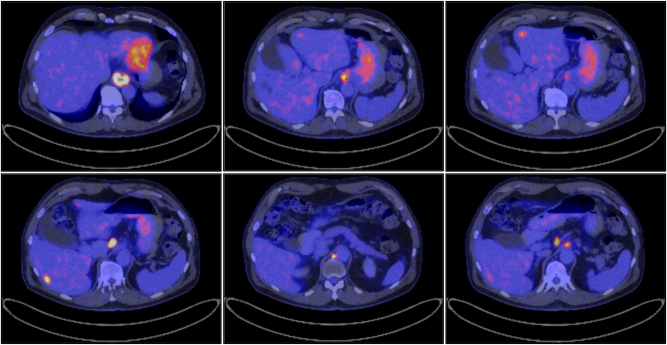

Abstract Image